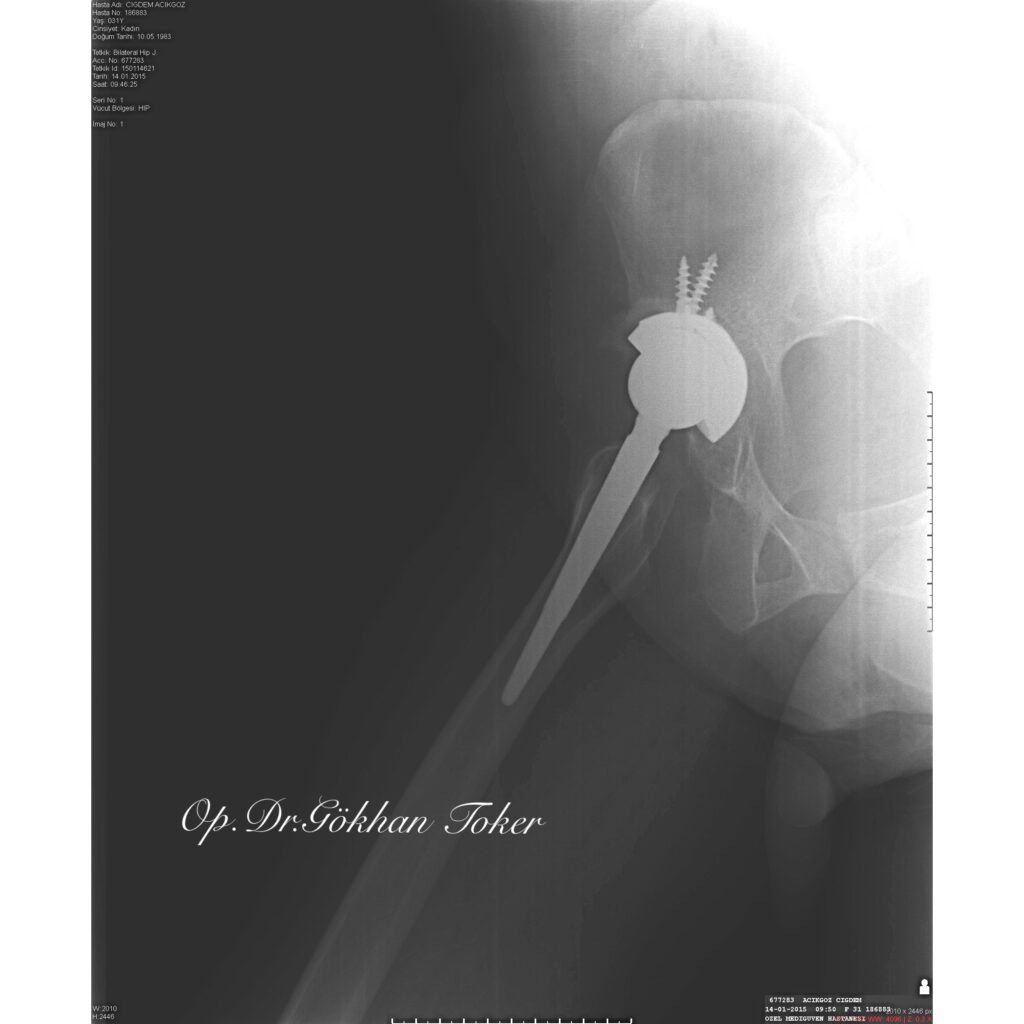

Ç.A.